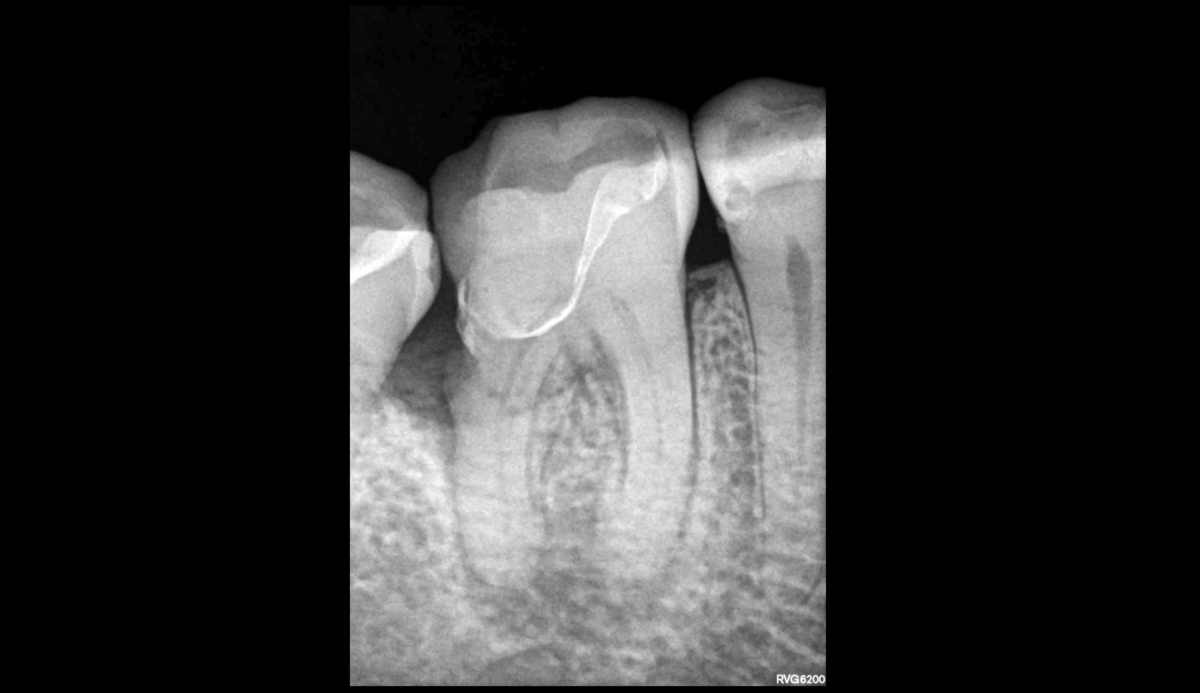

🔍 𝐋𝐞́𝐬𝐢𝐨𝐧 𝐞𝐧𝐝𝐨-𝐩𝐚𝐫𝐨𝐝𝐨𝐧𝐭𝐚𝐥𝐞 vraie, mixte ou combinée.

📍 𝐋𝐞́𝐬𝐢𝐨𝐧 𝐨𝐬𝐬𝐞𝐮𝐬𝐞 𝐚𝐩𝐢𝐜𝐚𝐥𝐞 d’origine endodontique.

📍 𝐋𝐞́𝐬𝐢𝐨𝐧 𝐢𝐧𝐭𝐫𝐚-𝐨𝐬𝐬𝐞𝐮𝐬𝐞 𝐝𝐢𝐬𝐭𝐚𝐥𝐞 d’origine parodontale, en rapport avec :

— la 𝐥𝐢𝐦𝐢𝐭𝐞 𝐭𝐫𝐞̀𝐬 𝐛𝐚𝐬𝐬𝐞 de la restauration,

— voire une 𝐥𝐞́𝐬𝐢𝐨𝐧 𝐜𝐚𝐫𝐢𝐞𝐮𝐬𝐞 𝐫𝐞́𝐜𝐢𝐝𝐢𝐯𝐚𝐧𝐭𝐞

— ou une 𝐫𝐞́𝐬𝐨𝐫𝐩𝐭𝐢𝐨𝐧 𝐞𝐱𝐭𝐞𝐫𝐧𝐞.